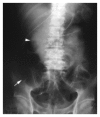

Results: Gender, the type of resection, operating time, blood loss, tumor status and amount of narcotics were comparable in the three groups. However, the group C patients were older than those in groups A and B (67.5+/-17.7 vs 56.8+/-13.2, 57.5+/-11.7 years, P = 0.048). First bowel flatus occurred after 4.35+/-0.93 d in group A, 4.94+/-1.37 d in group B, and 4.71+/-1.22 d in group C (P>0.05). Oral feeding of a soft diet was tolerated 7.21+/-1.92 d after operation in group A, 10.15+/-2.17 d in group B, and 7.53+/-1.35 d in group C (groups A and C vs group B, P<0.05). There was no significant difference in respect to the first flatus among the three groups. However, the time of tolerating oral intake with soft food in groups A and C patients was significantly shorter than that in group B patients. Levels of C-reactive protein (CRP) were significantly lower in group C and there was a more prominent and prolonged response in CRP level in patients undergoing IPC. The incidence of post-operative complications was similar in the three groups except for prolonged post-operative ileus. There was no increased risk of anastomotic leakage in patients receiving Met.